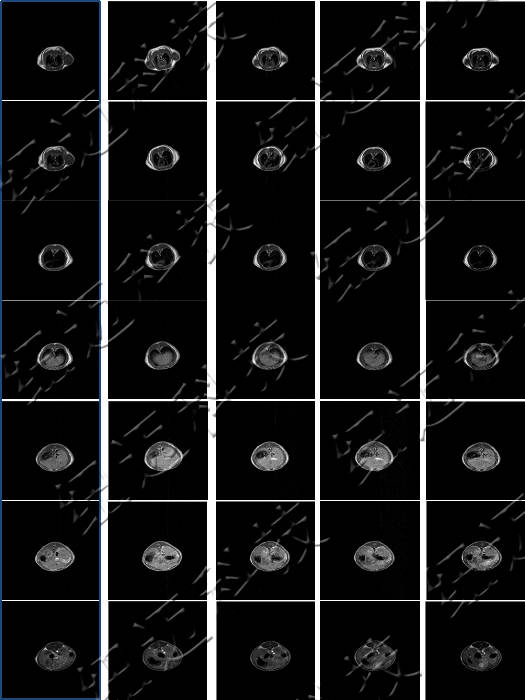

低场核磁共振技术在造影剂与动物成像中的应用

测试钆类MRI造影剂弛豫率测试以及造影剂样品的T1加权成像。

核磁共振成像因其具有无创、快速、高解析率、高对比度等特点,在临床上广为使用。特别是在肿瘤的诊断中,该技术利用病变组织和正常组织物理特性的不同而获得的结构、功能影像,已经成为原发肿瘤和肿瘤转移早期诊断中不可或缺的重要依据。